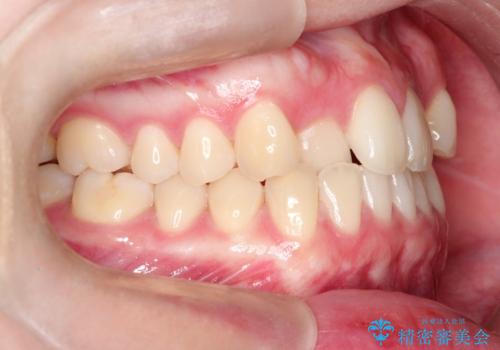

- 前歯のガタツキが気になるとのことで来院されました。

ワイヤー矯正とインビザライン矯正を併用することによって、治療期間の短縮と、より良い仕上がりを目指す治療を選択することとしました。

インビザライン(アライナー)矯正とワイヤー矯正のそれぞれの利点を生かした治療を行い、綺麗な歯並びになりました。